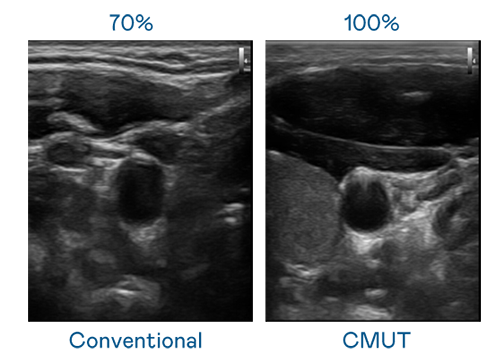

CMUT 技术是一种用电容式微机电元件来产生超音波讯号的技术。与传统 PZT 压电式技术相比,CMUT 频宽增加 30%,更宽频的超音波讯号让影像解析度大幅提升,是实现高影像品质医疗超音波扫描、促进精准医疗发展的关键技术。

超音波影像的解析度高低,首先取决于探头能发出的讯号频宽。AG集团 CMUT 可提供高清晰的超音波讯号,提供高频宽、高灵敏度、影像纹理细节更高的超音波影像,协助医护人员缩短影像判读时间及利用精准的医疗影像进行诊断。